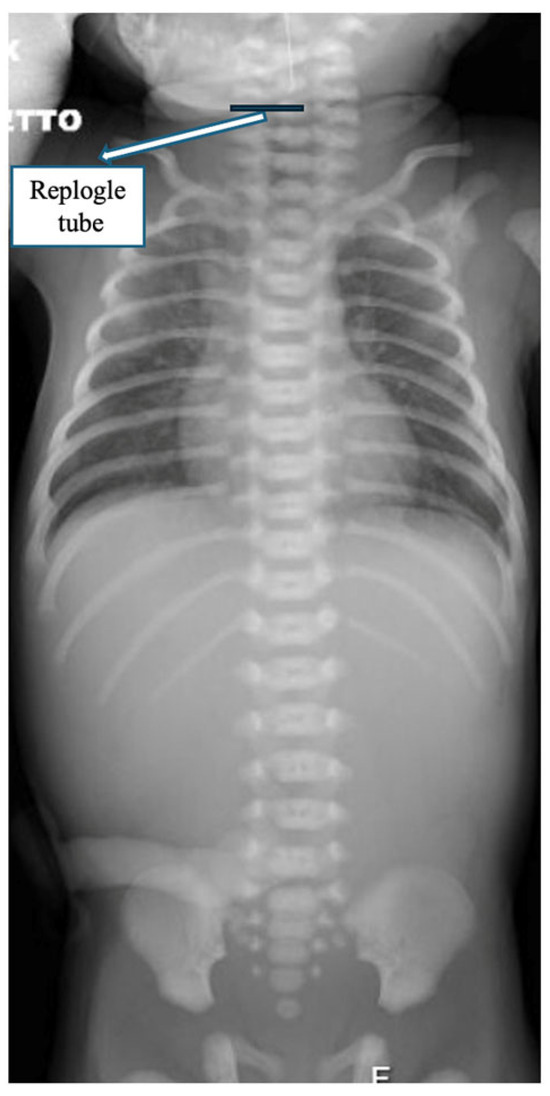

After 15 days, the patient was taken to the operating room for thoracoscopic exploration. Unexpectedly, a regular distal esophageal pouch was visualized, extending cranially up above the thoracic inlet and appearing to reach the cervical region (Figure 2).

The thoracoscopic assessment was performed with the aim of measuring the esophageal gap and evaluating the feasibility of primary anastomosis or internal traction with delayed primary anastomosis. However, intraoperative visualization of the distal esophagus extending into the thoracic inlet prompted reconsideration of the surgical plan (Figure 3).

Figure 2. Intra-operative findings: the lower esophageal pouch extending under the azygos vein ending very close to the upper esophageal pouch at cervical level.